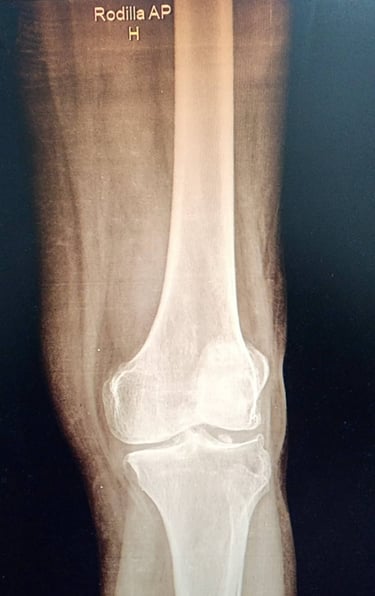

En muchos casos, es necesario recurrir a estudios de imagen para obtener una visión más clara del estado de la articulación. Existen diversas pruebas que permiten identificar muchos tipos de lesion como: fracturas, lesiones de ligamentos, lesión del cartílago, meniscopatias o lesiones de los meniscos, inflamacion, derrame articular . Asimismo, en ciertas situaciones, los estudios de laboratorio pueden ayudar a detectar enfermedades inflamatorias o afecciones de la rodilla.